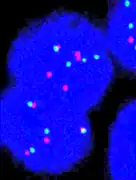

Fluorescence in situ hybridisation

FISH can be used to measure the number of copies of the gene which are present and is thought to be more reliable than immunohistochemistry.[47] It usually uses chromosome enumeration probe 17 (CEP17) to count the amount of chromosomes. Hence, the HER2/CEP17 ratio reflects any amplification of HER2 as compared to the number of chromosomes. The signals of 20 cells are usually counted.

-

This cell displays 2 signals of HER2 (red) and 3 signals of CEP17 (green)

This cell displays 2 signals of HER2 (red) and 3 signals of CEP17 (green) -